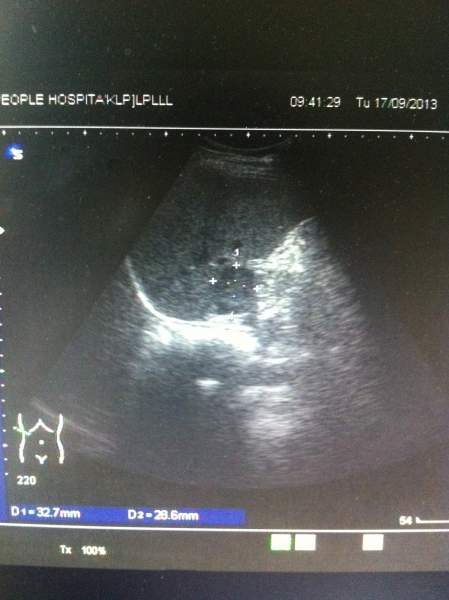

超声图像,各位大侠帮忙看下,肝上的这块是不是占位? 已有2人参与

患者今天前到我单位体检,两月前在另一单位体检过,结果正常,这次看肝上像有异常回声,让她再去上级单位复查,第二天患者去了,复查结果说是正常。 难道我们图像显示的是肝尾叶?回声可以这么低吗?看着还有边界的样子,难道是部分容积效应?真心很纠结,求指教,谢谢! IMG_1411.JPG IMG_1412.JPG IMG_1413.JPG IMG_1416.JPG |